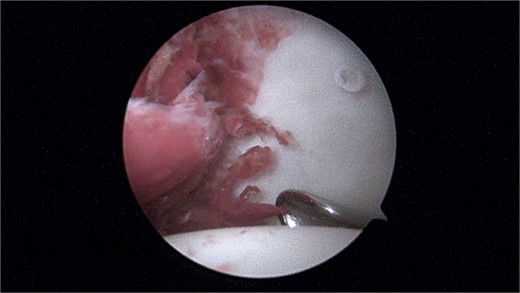

Magnetic resonance imaging (MRI) of the hip revealed a well-defined intra-articular mass with extensive synovial thickening (Fig. 1). Given these findings, the patient underwent hip arthroscopy to remove the mass and perform a histopathological examination.

MRI is observed in axial, sagittal, and coronal sections, showing the presence of an intra-articular lesion and abundant synovitis.

During the arthroscopic procedure, extensive synovial proliferation and a well-defined mass were identified within the joint space. The mass was excised, and the synovium was sampled for histopathological evaluation (Fig. 2). The pathology report confirmed the diagnosis of an SGCT, a rare entity within the hip joint (Fig. 3).